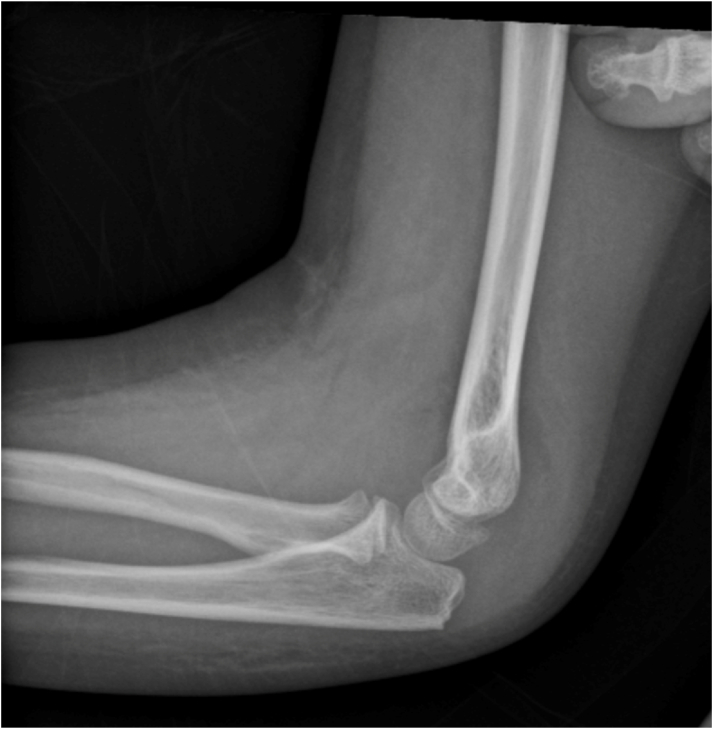

Case: A 7-year-old girl presented with a painful effusion in her right knee, fever, and a negative joint aspirate. One week later, she presented again with an effusion in her left elbow, elevated inflammatory markers, and a joint aspirate that raised concerns for septic arthritis. Irrigation and debridement of the elbow were performed, and the cultures returned negative results. Subsequently, the child experienced ongoing migratory polyarthropathy over several months, which was ultimately identified as leukemia. The initiation of chemotherapy resolved her symptoms. Although the orthopaedic literature is limited, leukemic arthritis should be considered in the differential diagnosis for a pediatric patient with a painful, swollen joint, especially when symptoms migrate without a clear cause.

Key concepts: (1)Leukemic arthritis appears as a painful, swollen joint that is clinically similar to septic arthritis, based on both examination and serum and synovial laboratory values.(2)A prompt diagnosis of acute leukemia is essential as leukemic arthritis can be the first presenting symptom.(3)Recognizing and understanding leukemic arthritis is essential for orthopaedic providers to ensure the timely diagnosis of leukemia and prevent unnecessary procedures and surgeries for these children.